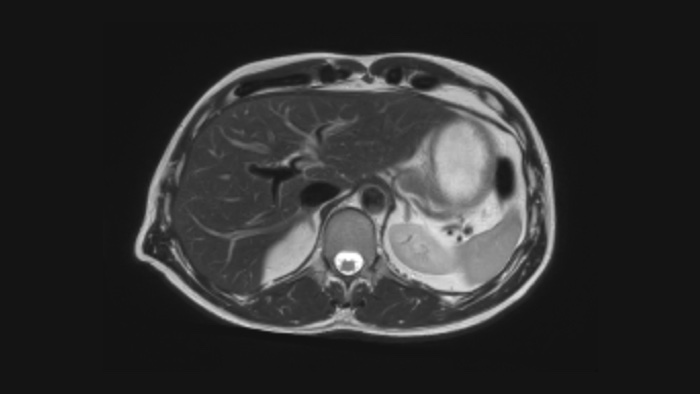

SmartSpeed SmartSpeed AI enables to decrease the scan time up to 65% with equal or better image quality

Diagnostic confidence Expand your imaging capabilities in all clinical areas. See how your peers are benefiting.

Speed & Comfort Provide up to 40% reduction in breath holds, with virtually equal image quality4.